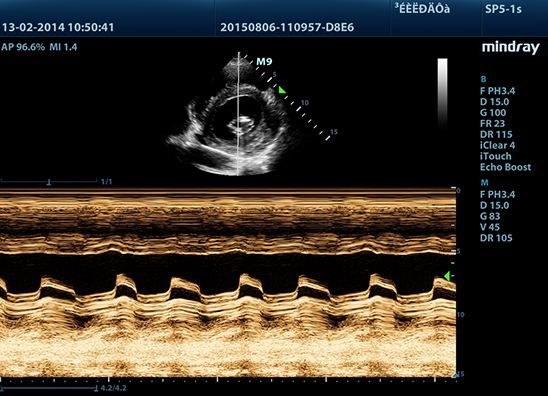

Mindray M9 je dopplerovský ultra ľahký prenosný UZV prístroj najvyššej High End triedy s použitím single crystal 3T sond (vynikajúce zobrazenie blízkeho i vzdialeného poľa), HDR FLOW, ECHO BOOST, Natural Touch Elastography, kontrastného zobrazenia, TDI. Špeciál hlavne pre kardiológiu.

Klinické obrázky: